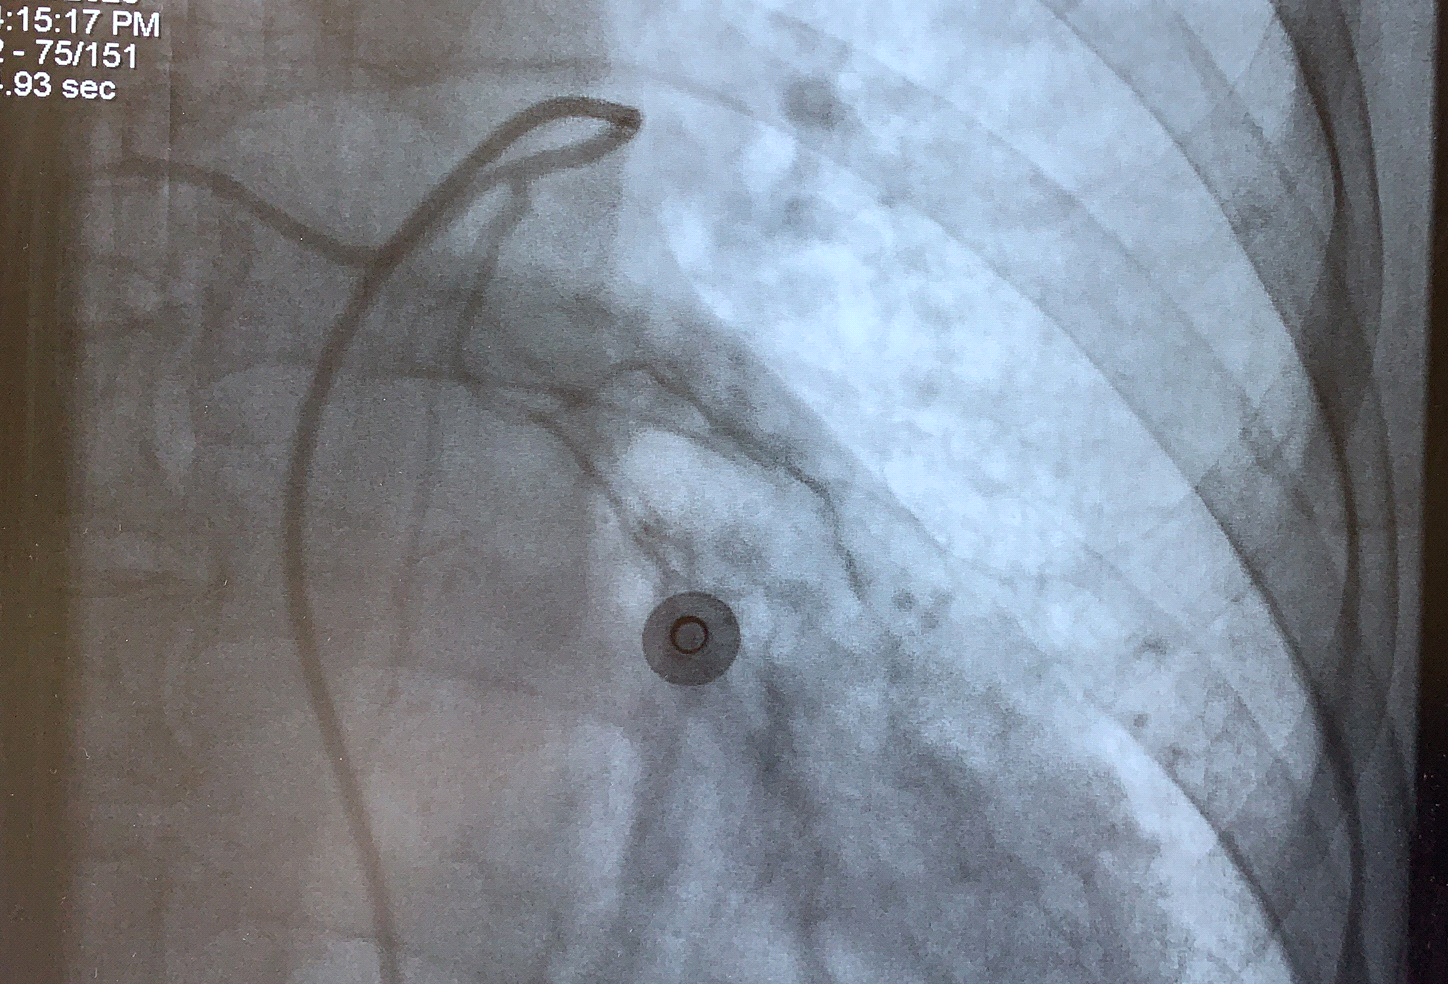

患者被送入介入治療室,術(shù)中造影發(fā)現(xiàn)雙側(cè)支氣管動(dòng)脈細(xì)小分支均破裂出血,予以選擇進(jìn)入后栓塞血管床,栓塞完后造影支氣管動(dòng)脈遠(yuǎn)端未見(jiàn)顯影。術(shù)后患者未再咯血,無(wú)特殊不適,無(wú)并發(fā)癥,手術(shù)成功。